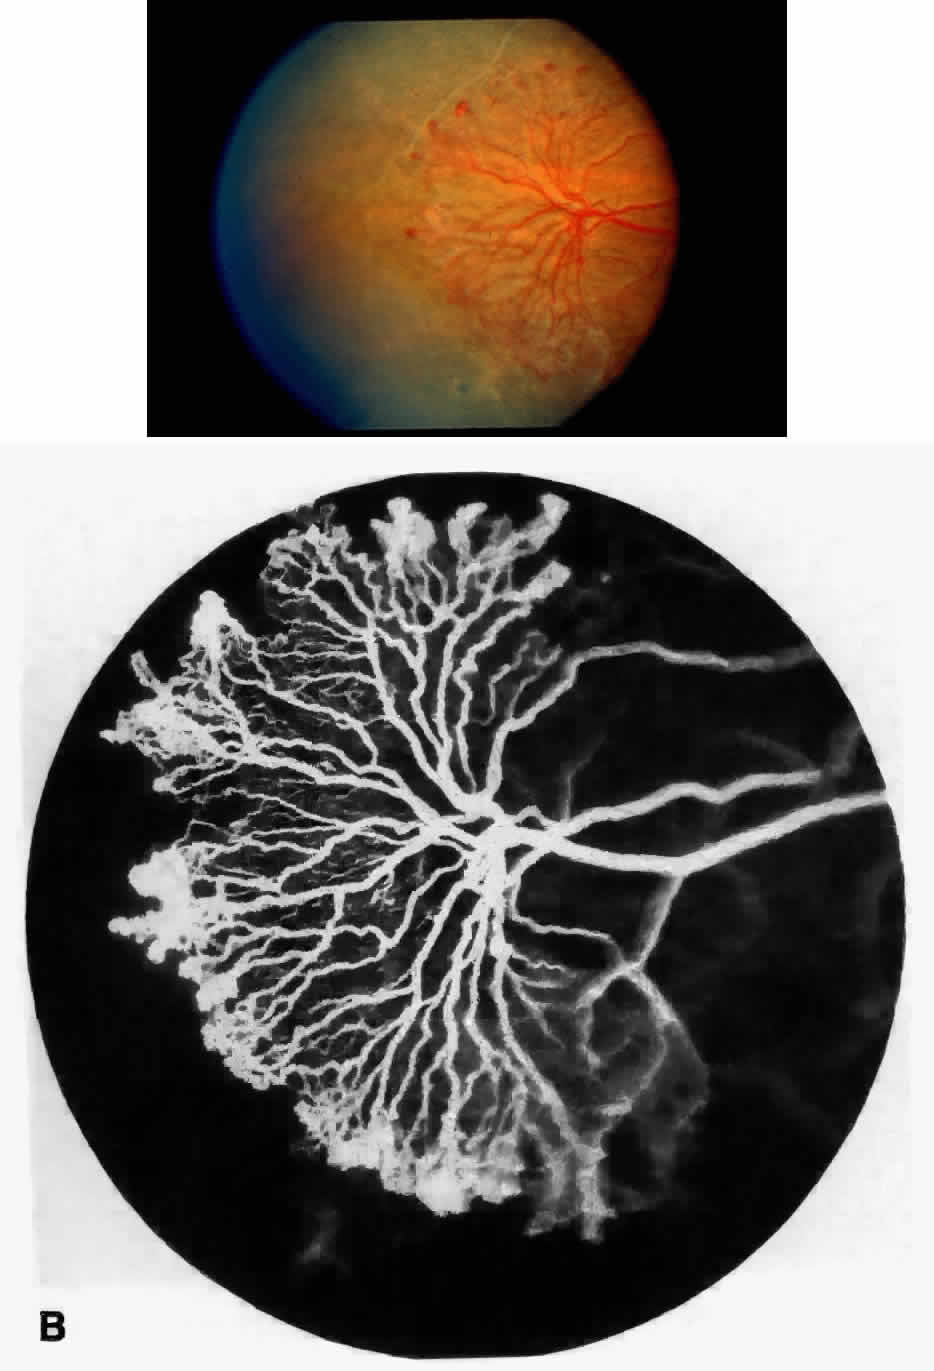

STAGE III: PRERETINAL NEOVASCULARIZATION (PROLIFERATIVE SICKLE RETINOPATHY). “Sea fan”-shaped neovascularization typically develops on the venular side of an arteriolar-venular anastomosis, mimicking the normal development of retinal capillaries (Fig. 24).125 A lowered oxygen tension and angiogenic factors released on the venular side may be the stimulus for neovascular growth.125,126 In most instances, the direction of growth is toward the ora serrata, from the perfused retina toward the nonperfused retina. Presumably, this represents an abortive attempt to revascularize the nonperfused retina, initiated by vasoproliferative factors.

The characteristic neovascular lesions of PSR are called sea fans because they resemble the marine invertebrate Gorgonia flabellum.70 They tend to occur more commonly in the temporal periphery, but they have been reported to occur in the temporal macula in the presence of extensive nonperfusion.130,133 Initially they grow on the surface of the retina, but they often become elevated into the vitreous and adhere to a partially detached posterior hyaloid.114 It may be difficult to visualize small sea fans ophthalmoscopically; however, fluorescein angiography clearly demonstrates leakage of dye into the vitreous (Fig. 25). The feeding arteriole is usually more tortuous than the draining venule (Fig. 26). Early on, the neovascular lesion is fed by a single arteriole and drained by a single venule, but with time, additional arterioles and venules become arborized within the lesion (Fig. 27).129 Growth of the sea fan often occurs circumferentially, rather than radiallyÜmh- 1Ý, toward the ora serrata. Progressive circumferential growth may lead to neovascular lesions extending around the entire periphery. As it matures, a white fibroglial mantle often covers the neovascular tissue (Color Plate 2B).

|

PSR is associated with the severe vision-threatening sequelae of sickle cell disease: vitreous hemorrhage (stage IV) and retinal detachment (stage V). These stages are believed to result from transudation of blood components into the vitreous through the incompetent neovascular tissue (Fig. 28). Vitreous fluorophotometry has quantified the leakage from the peripheral neovascularization.134 This leads to premature syneresis and collapse of the vitreous, inducing tractional forces on the retina that lead to vitreous hemorrhage, retinal tears, and tractional and rhegmatogenous retinal detachment. In rare cases, an exudative detachment may occur.

|